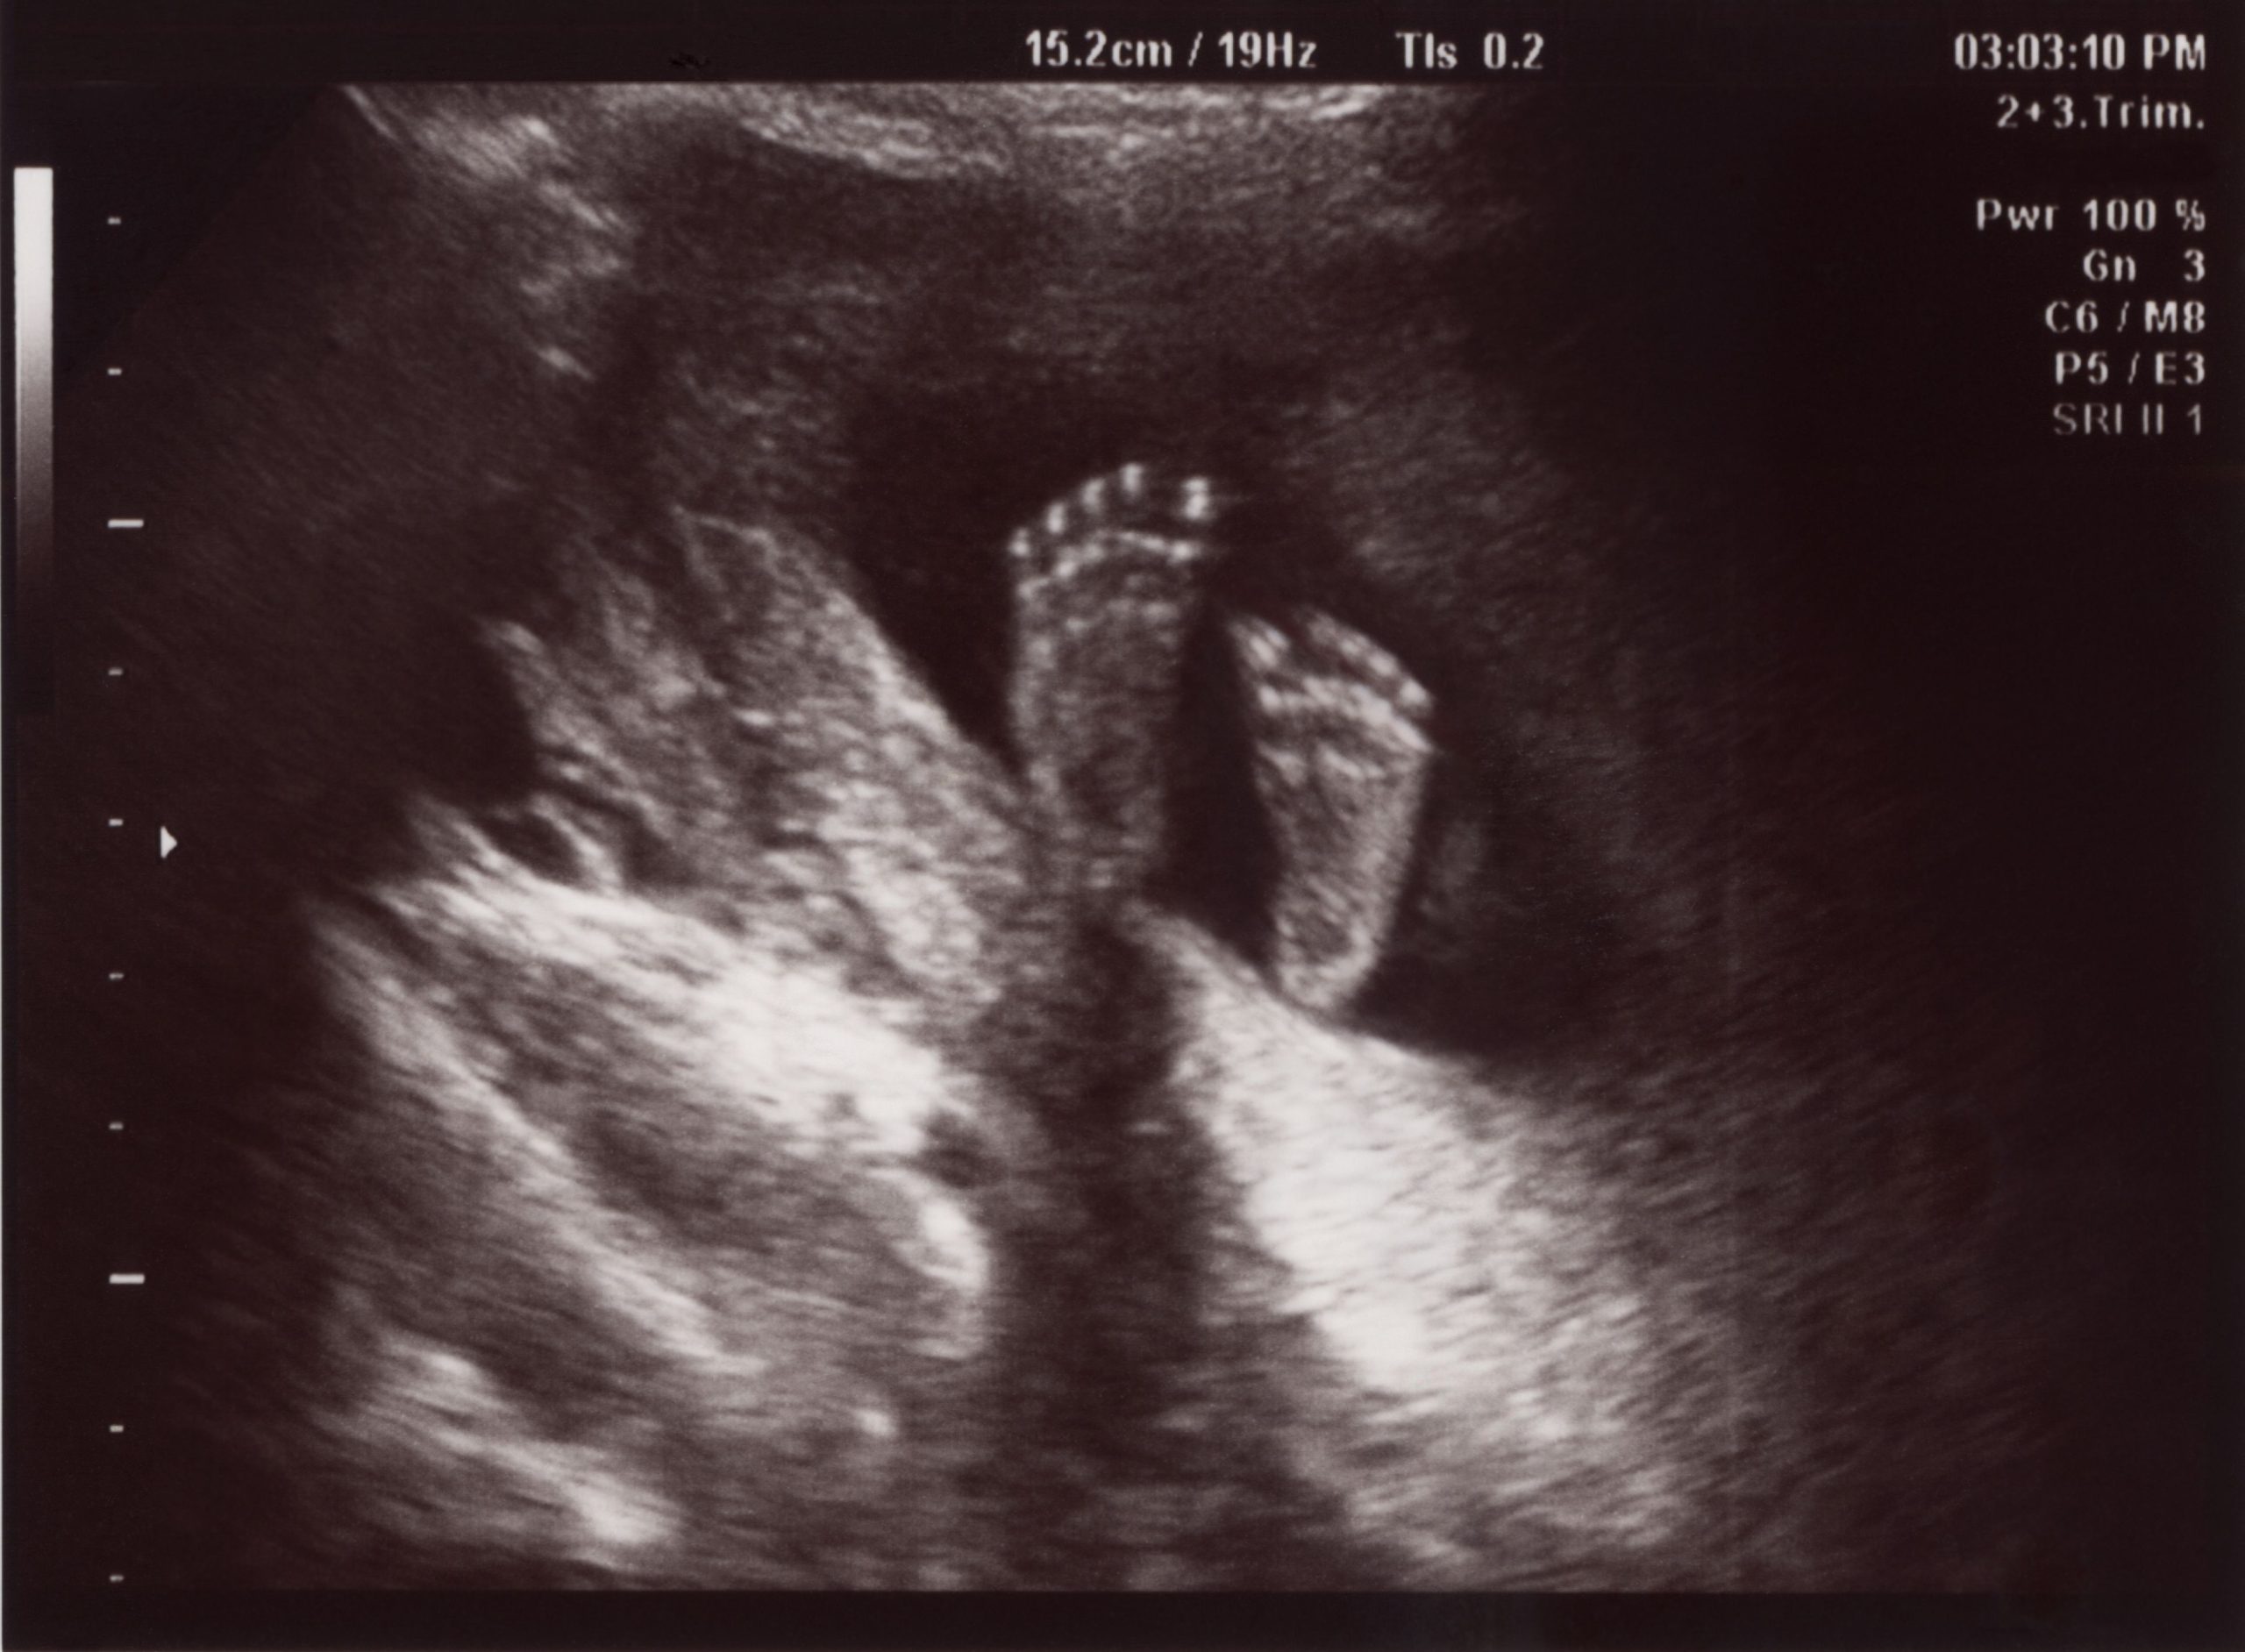

В современном мире каждая будущая мамочка обязательно проходит процедуру УЗИ при беременности с целью исследования развития плода. На сегодняшний момент самым популярным как у беременных женщин, так и у специалистов является безвредный и надежный метод диагностики трехмерный ультразвуковой скрининг. Обычно при беременности назначается как минимум три таких УЗИ исследований. Но может быть конечно намного больше, особенно если есть какие-то проблемы или опасения в протекании беременности и развитии плода.

В конце первого триместра беременности необходимо провести следующее скрининговое исследование. Его задача заключается в том, чтобы обнаружить пороки развития плода. На этом сроке беременности можно обнаружить симптомы тяжелых хромосомных отклонений, к которым относятся синдромы Эдвардса, Дауна. На сроке 9-11 недель можно определить ноги и руки плода, структуру мозга, позвоночник, сердце, мочевой пузырь, желудок, а также движения плода. На этом сроке беременности можно делать фото- и видеосъемку плода. Подробнее о развитии плода на сроке 10 недель.

Наиболее полную картину пороков сердечного развития можно наблюдать во время процедуры УЗИ на сроках до 24-25 недель беременности. На этом сроке сердце полностью сформировалось, развилось до нужных размеров, ребра не сильно уплотнились и они не образуют акустических теней, мешающих проводить осмотр сердца. УЗИ обследовании на сроке 23-25 недель является обязательным. Кстати, на 25-й недели беременности можно уже проводить допплеровское исследование кровообращения.

К этому моменту плод имеет уже достаточно большие размеры, чтобы можно было тщательным образом оценить его строение на предмет наличия/отсутствия пороков. Поэтому это УЗИ еще называют анатомическим. В этом периоде оценивается состояние внутренних органов плода, врачи определяют соответствуют ли размеры плода сроку беременности, выявляются врожденные пороки развития, оценивается состояние плаценты. При выявлении каких либо отклонений в это сроке врач сможет своевременно оказать лечение.

Третье обязательное УЗИ исследование с допплером делается на 32-34 неделе. Определение параметров роста плода и повторная оценка анатомии плода. Определяют предлежание плода, то есть как он расположен в матке, как будет рождаться, можно оценить есть ли внутриутробная задержка развития плода, оценивается его вес, рост. На этом сроке беременности диагностируются поздно выявляемые уродства, те, которые не всегда удается увидеть при УЗИ на ранних сроках. Оценивается состояние плаценты.